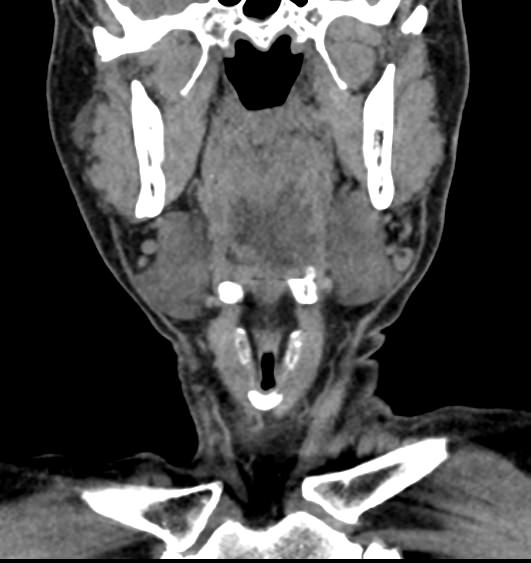

Используемые в нашей клинике томографы, благодаря своему оснащению, позволяют получать снимки высокого качества и детализации за короткий промежуток времени, что минимизирует уровень лучевой нагрузки на организм. Используя полученные данные, аппараты создают трехмерные реконструкции анатомической зоны. Это дает возможность наглядно оценить пространственное соотношение лимфатических узлов и близлежащих органов, выявить прорастание в окружающие ткани, особенно при образовании цепочек, пакетов и конгломератов лимфоузлов.

Для повышения качества визуализации лимфоузлов, особенно при подозрении на онкологических процесс, исследование проводится с внутривенным болюсным контрастированием. Контрастный препарат, содержащий йод, вводится в вену с помощью автоматического шприца. Распространяясь по сосудистой системе, препарат накапливается в патологических очагах, в том числе, в измененных лимфоузлах, и увеличивает их яркость на КТ-изображениях. Методика контрастирования помогает выявлять опухоли минимальных размеров, проводить дифференциальную диагностику между доброкачественными и злокачественными новообразованиями и воспалительными изменениями.

Мультиспиральная КТ позволяет оценить размеры лимфатических узлов, выявить деформацию их контуров, неоднородность структуры, установить точную локализацию, взаимодействие с близлежащими органами и окружающими тканями, обнаружить инфильтрацию прилегающих структур.